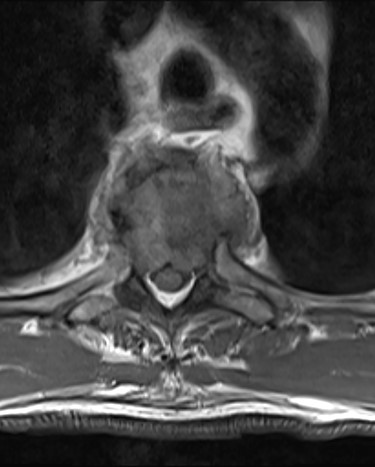

Spinal images are presented in Figs 1–6. Cross-sectional imaging revealed no other neoplastic lesion. He received dexamethasone 10 mg bolus then 4mg four times daily with appropriate proton pump inhibitor coverage. Due to no distinguishable major arterial feeder upon review of the imaging jointly with the neuroradiologist, pre-operative embolization was not attempted. The following morning, he underwent posterolateral right costotransversectomy, ligation of the ipsilateral T4 nerve root, T4 vertebrectomy and insertion of an expandable titanium cage with T1–T7 pedicle screw fixation (Figs 7 and 8). Post-operatively his pain improved to VAS 2/10 and motor power in his left lower limb improved to MRC grade 4/5. The patient was discharged home Day 10 post-admission with physiotherapy.

Sagittal T2-weighted magnetic resonance image (T2W MRI) with T4 metastatic epidural spinal cord compression (MESCC) and a synchronous T10 lytic lesion.

The patient presented with thoracic kyphosis and clinical evidence of mechanical pain. The radiological images showed evidence of three-column involvement of the T4 lytic lesion. Adjacent bilateral pedicle fracture of T5 offered no additional structural support and therefore this degree of deformity was not surprising. This spinal instability neoplastic score (SINS) [3] of 14/18 and grade 3 epidural spinal cord compression (ESCC) [2] were in support of surgical decompression and stabilization [2, 3]. A number of approaches were considered including anterior transcavitary, posterolateral extrapleural approaches and posterior decompression and instrumentation, with or without insertion of expandable titanium cage [1]. Laminectomy alone or with radiotherapy was not an option in this case as it would have offered very little decompression of this anteriorly compressing lesion as well as exacerbate the deformity by further sacrificing the posterior elements, thereby offering no contribution at structural stability.